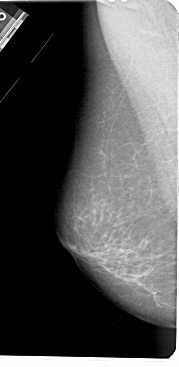

A_1433_1.RIGHT_MLO

LEFT_MLO LINES 5491 PIXELS_PER_LINE 2671 BITS_PER_PIXEL 12 RESOLUTION 43.5 NON_OVERLAY